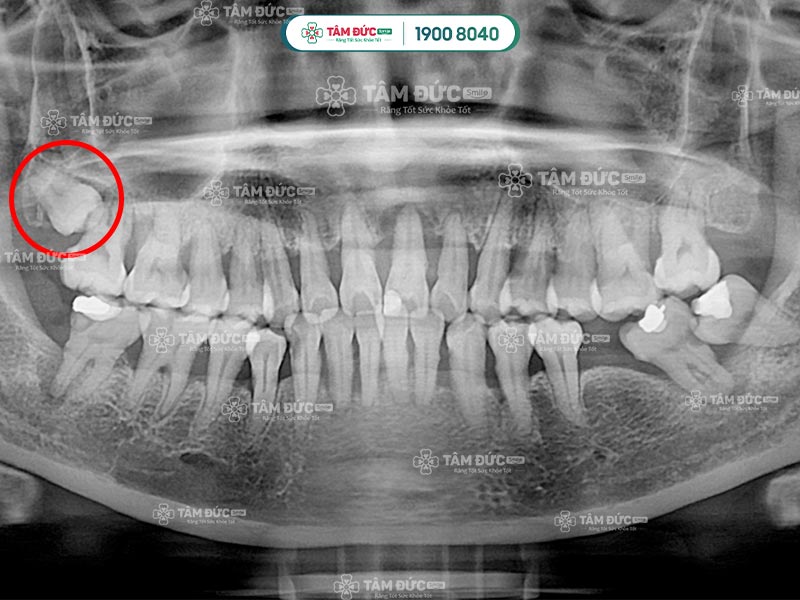

Trên cung hàm, răng khôn là chiếc răng số 8, mọc sát vách hàm và nằm ở trong cùng hàm răng. Răng khôn mọc sát răng số 7, Quý khách sẽ có 4 chiếc răng khôn chia đều cho cả hàm trên và dưới.

Răng số 8 sẽ gây đau trong các trường hợp mọc ngầm, mọc lệch, mọc đâm vào răng số 7,... Mặt khác, sự phát triển của răng khôn cũng làm cho bề mặt nướu bị phá vỡ, từ đó gây đau nhức dai dẳng. Sở dĩ mọc răng khôn gây đau vì lúc này xương hàm đã phát triển hoàn thiện, không đủ chỗ cho răng khôn mọc lên.